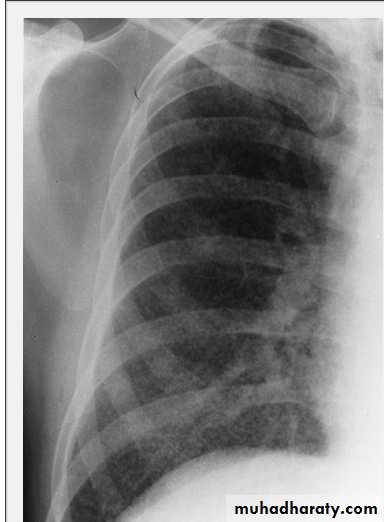

Massive pleural effusion with mediastinal shift to the left.

(A) Chest radiograph

(B) CT coronal reconstruction. A massive effusion displaces the mediastinum to the left. CT shows the important pleural effusion together with the enhanced atelectatic left lung.

Note also the depression of the right hemidiaphragm (arrows).